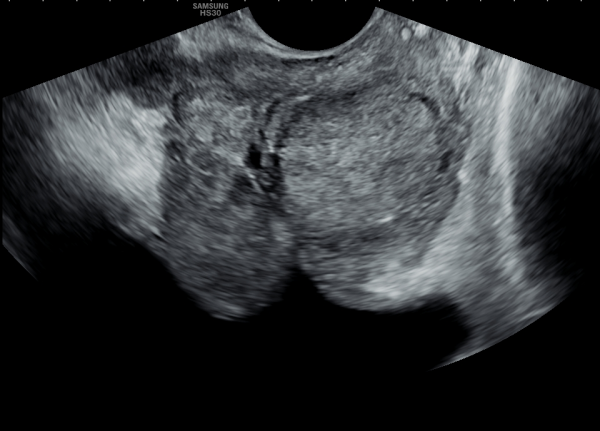

10년전부터 배뇨장애와 빈뇨로 비뇨기과에서 약을 복용중 2년전부터 급박뇨와 요실금이 심해져 투약을 했으나 증상의 호전이 없다고 내원당일 검사한 경직장 전립선 초음파 검사상 전립선 비대와 전립선의 낭종과

사정관주위의 결석이 관찰되는 경직장 전립선 초음파 사진입니다.

This is a transrectal prostate ultrasound image taken on the day of the visit. The patient had been taking medication for urinary difficulties and frequent urination for over 10 years at a urology clinic. However, since two years ago, symptoms of urgency and urinary incontinence worsened despite continued medication. The ultrasound shows prostate enlargement, cysts within the prostate, and calcifications around the ejaculatory ducts.